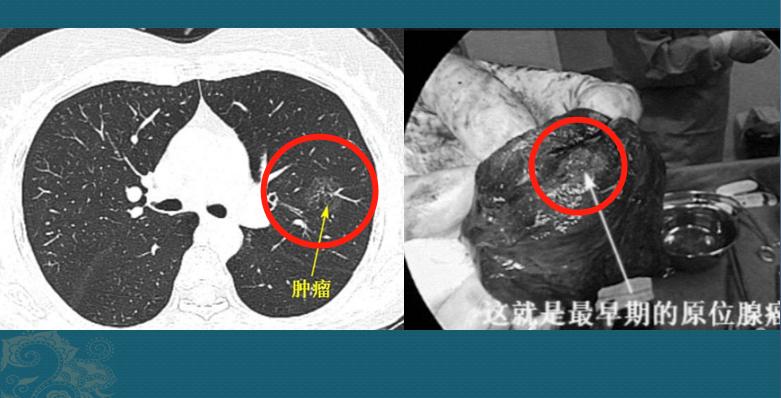

病例2,磨玻璃结节2.6cm,原位腺癌

这是一位50多岁的女士,体检发现左肺磨玻璃结节,2.6cm手术病理原位腺癌:

朋友们没看错,2.6cm,原位癌,≤3cm,癌细胞完全贴壁生长,无间质、血管和胸膜浸润;如果肿瘤被完整切除,5年生存率为100%。